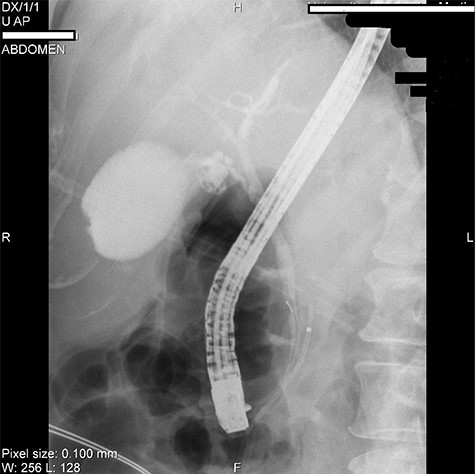

We present the case of 46-year-old female patient suffering from spontaneous hypoglycemia. She was admitted to our hospital due to worsening clinical symptoms. At first, she underwent a 72-hour monitored fast and biochemical testing for endogenous hyperinsulinism, which proved positive. Once the other causes of spontaneous hypoglycemia were excluded, we started the process of localization of insulinoma. Then the patient underwent endoscopic ultrasonography (EUS) of pancreas with the find of hypoechogenic, well demarcated, hypervascular tumor in the head of pancreas size of 12.4 × 10.5 mm (Fig.1). Computed tomography (CT) examination of abdomen followed up and tumor of pancreatic head, corresponding with the diagnosis of insulinoma, was found (Fig. 2). It was located nearby pancreatic and biliary duct. Because of serious clinical symptoms, an early surgical treatment was indicated. Based on the evaluation of the surgeon to perform the less radical surgery, it was suggested to enucleate the tumor with preoperative stenting of pancreatic and biliary duct. Two days before the surgery, ERCP with insertion of pancreatic and duodenobiliary stent was performed (Fig. 3). With regard to the patient's preference and overweight, laparotomic approach was selected. Determination of the exact position of tumor was difficult, insulinoma was hardly palpable. We used intraoperative ultrasonography to identify the exact location of tumor (Fig. 4). Then the surgeon palpated the inserted stents and the insulinoma was identified intrapancreatically, 3–4 mm nearby pancreatic and bile duct. Enucleation of tumor was performed by harmonic scalpel (Fig. 5). During the surgery, the right position of stents was verified by touch. After enucleation, there was no presence of bleeding, the defect was filled with tissue glue (Fig. 6). Macroscopically, tumor was round shaped, well capsulated, size 1 cm (Fig. 7). During postsurgery period, the patient was stable and with no signs of complication. On the sixth postoperative day, endoscopic removal of pancreatic stent was carried out. Patient was discharged from the hospital on the eight postoperative day. Duodenobiliary stent was left in ductus choledochus for 1 month.

ERCP picture of inserted stents in pancreatic (near the arrow) and bile duct.